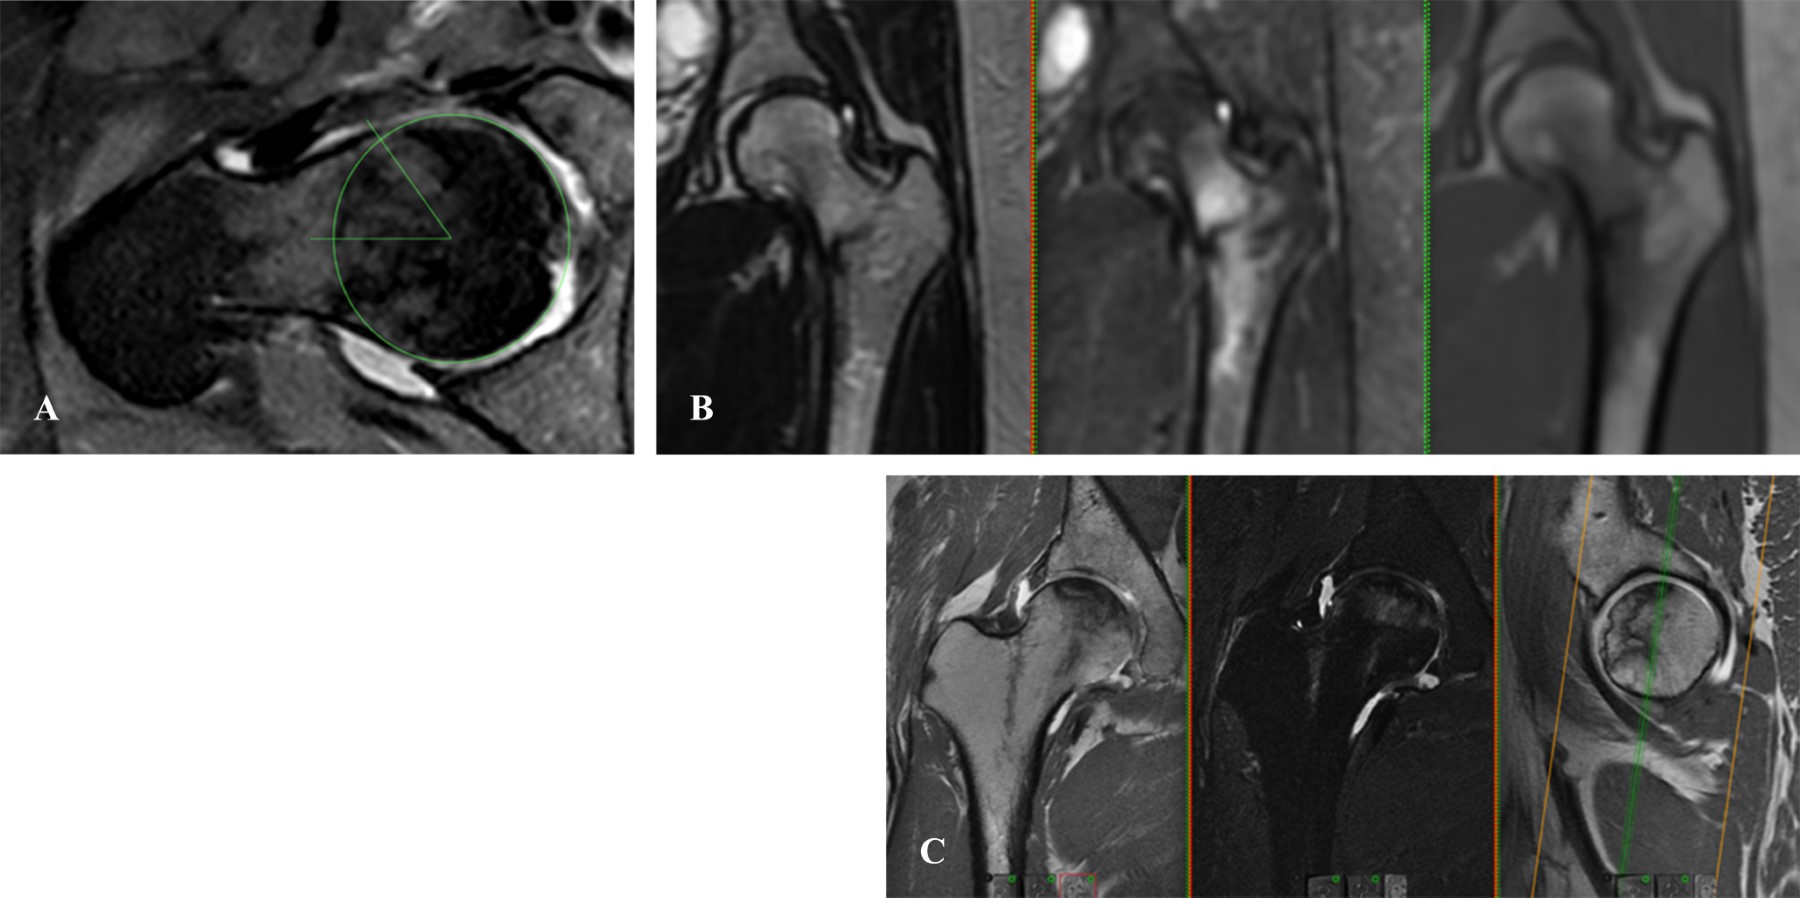

Figure 3

The painful hip has been a topic of study that has evolved from the beginning of the last century to the present. The clinical approach is complex, and requires a systematization process associated with good questioning, clinical maneuvers with their corresponding interpretation, and complementary imaging studies. The understanding of hip pathology, especially in young adults, is highly simplified and sometimes underdiagnosed, therefore, not treated in a timely manner. The prevalence of painful hip is more common in males (49 to 55%) than in females (25 to 28%), and the causes may vary according to demographic characteristics and the history of each patient. Bryan Kelly, made a topographic and anatomical description of the approach to the painful hip according to the theory or system of the layers: I. Osteochondral layer; II. Inert layer; III. Contractile layer; and IV. Neuro-mechanical layer. This system helps us understand the anatomical site of pain and its clinicopathological correlation. The semiological approach to hip pain is the fundamental pillar for differential diagnosis. We can divide it according to its topography into anterior, lateral and posterior, as well as according to its chronology and characteristics. The physical examination should be carried out systematically, starting from a generalized inspection of gait and posture to the evaluation of specific signs for alterations in each layer, which evoke pain with specific postures and ranges of mobility, or weakness and alterations in the arc of mobility of the joint. Image evaluation is initially recommended with radiographic projections that evaluate different planes, both coronal, sagittal and axial, complemented with panoramic views, and eventually dynamic sagittal ones if necessary. Requesting specific studies such as tomography to evaluate bone structure and reserve, or simple MRI when there is suspicion of soft tissue affection, or failing that, arthroresonance for joint pathology, will depend on the clinical symptoms and radiographic findings.